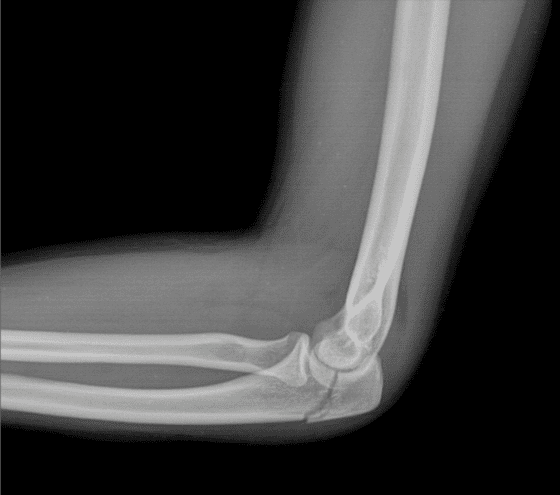

@EmergMedDr @mark_tehan @DrLindaDykes @Medic_Russell @AndyNeill @precordialthump @EMManchester @RCEMPolicyVP @EMTAcommittee @richardbody @LWestafer @docib @dnepo @srrezaie @First10EM Doing bloods on this cohort is hardly ever useful. I often find myself wondering which patients need as CT head, though